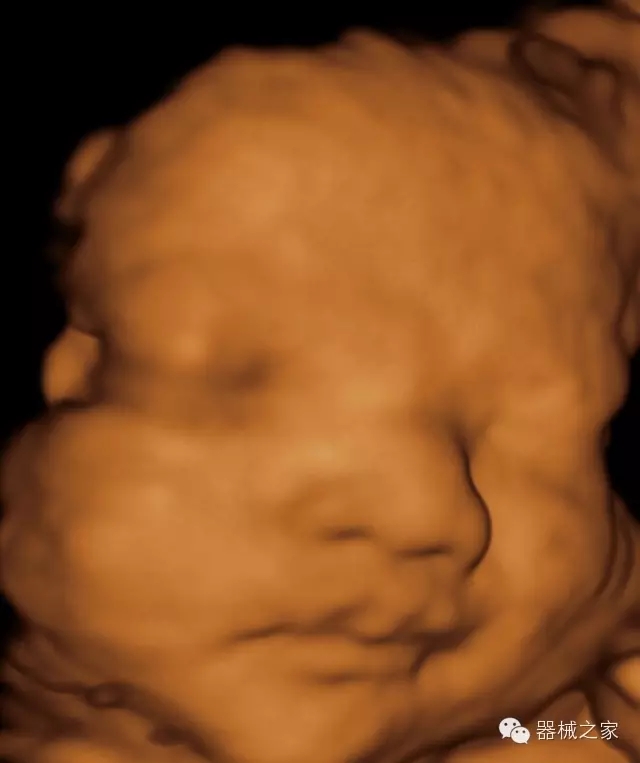

臨床圖片賞析

·完整的3D/4D臨床應用,STIC, MCUT 和Auto NT等滿足產(chǎn)科所有應用;

·更高的HQ羊膜腔鏡成像技術精細觀察每一個暗區(qū)細節(jié);